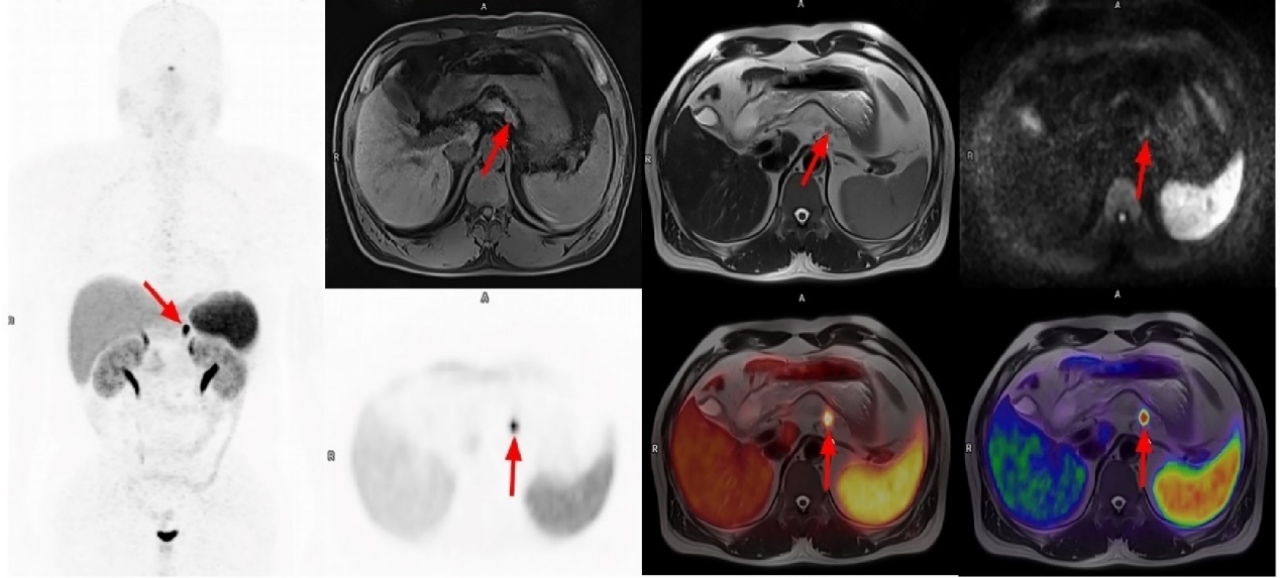

疑难杂症的“狙击手”

PET-MR除常规的代谢显像,更结合⁶⁸Ga等多种新型分子探针(像“生物导弹”一样精准定位),它对前列腺癌、神经内分泌肿瘤、血液系统肿瘤等具有极高的诊断价值,让微小病灶无所遁形。

▲54岁男患者,胰腺体部微小神经内分泌肿瘤影像